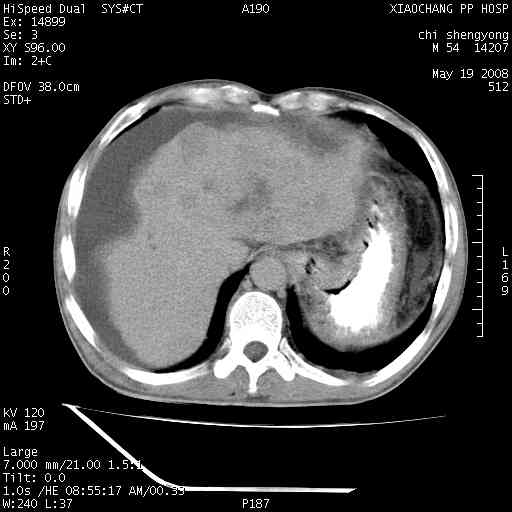

以下是引用zjzjr在2008-5-21 10:52:00的发言:[br]肝左叶巨块型肝癌伴门静脉左支瘤栓形成.肝硬化、腹水,胃底静脉曲张,脾术后改变。

以下是引用随光逐影在2008-5-21 16:20:00的发言:[br]1)肝左叶肝癌伴门静脉左支瘤栓形成,腹膜后淋巴结转移。2)肝硬化、腹水、胃底静脉曲张。3)胆囊炎。4)脾脏缺如,为切除术后所致。